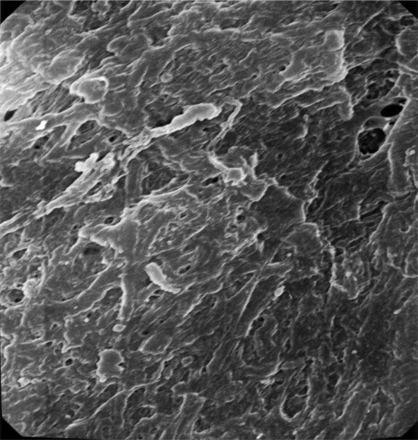

两个不同的结构模式与SEM可以认出:1)血栓展示先进成熟,所有的血栓性元素是如此密集集成单个实体没有清晰可辨的(图2),表明心脏稳定位置,持续暴露在剪切流;和2)血栓显示不同的纤维蛋白,红细胞被困,表明相对宽松的交联,一个活跃的地区特点的血栓仍在成熟的过程中,可能停滞的地区形成和再循环(图3)。这些模式被认为在不同比例在不同的患者。在某些情况下,可以联系具体的超微结构的研究结果推测病因的中风。值得注意的是这样一个广泛的血栓被恢复。